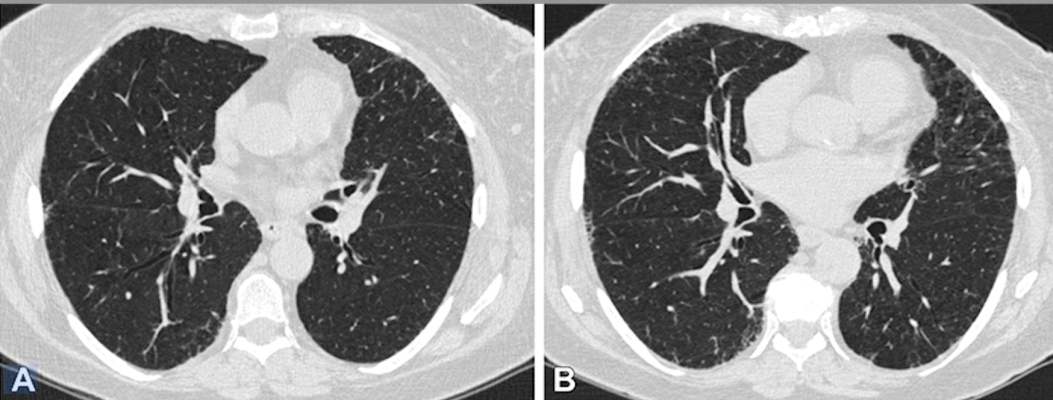

A recently-published study, “Association of Acute Respiratory Disease Events with Quantitative Interstitial Abnormality Progression at CT in Individuals with a History of Smoking,” found that in individuals with a history of smoking, progression of quantitative interstitial abnormalities (QIA) at CT was associated with severe acute respiratory events, independent of comorbidities, such as emphysema and small airway disease. The study was published in published in Radiology, a journal of the Radiological Society of North America (RSNA). Image courtesy: RSNA

Quantitative interstitial abnormalities (QIA) are subtle abnormalities on chest CTs that do not meet the diagnostic criteria for advanced pulmonary diseases but are nonetheless associated with decreased lung function and capacity, increased respiratory symptoms and death.

“QIA includes features like reticulation and ground-glass opacities as well as subtle density changes with important clinical implications,” said Bina Choi, M.D., associate physician in the Division of Pulmonary and Critical Care Medicine at Brigham and Women’s Hospital and postdoctoral fellow at the Applied Chest Imaging Laboratory, Harvard Medical School in Boston. “In some patients, QIA may be a precursor to advanced diseases such as pulmonary fibrosis or emphysema.”